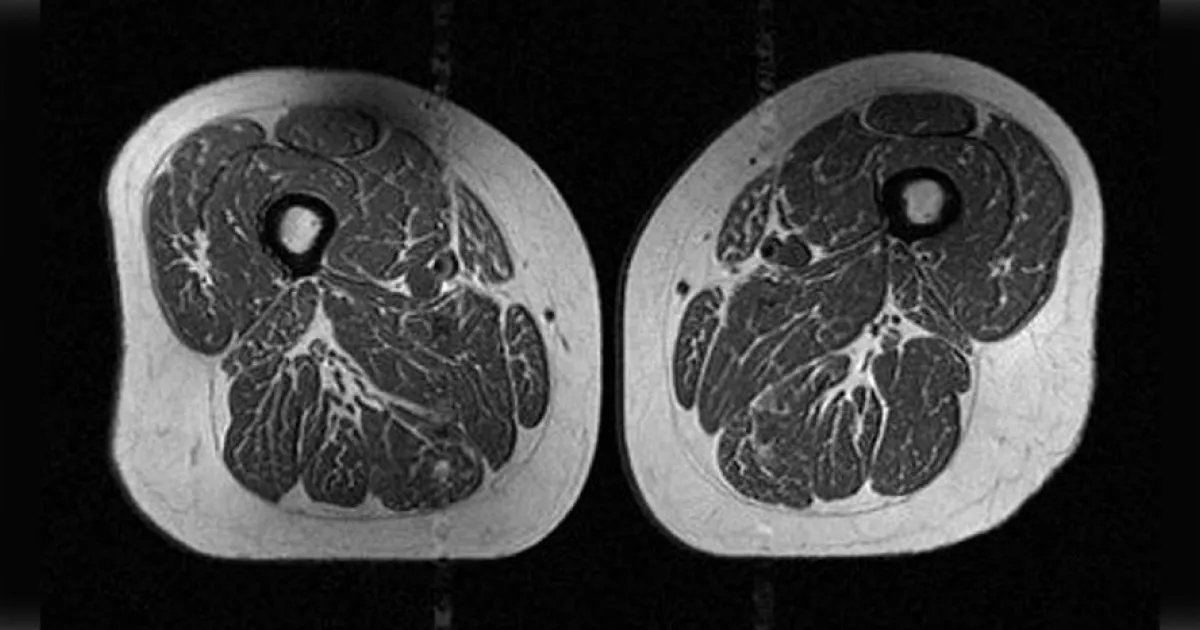

一名常吃即食穀片、糖果棒、含糖飲料等超加工食品的62歲女性,在經過MRI掃描後,拍下一張大腿肌肉夾雜著均勻脂肪,看起來就像「雪花牛排」的紋路。這種脂肪存在於器官組織中的狀態,被醫界稱為「脂肪浸潤」,會阻礙肌肉生長,導致肌肉無力,是罹患退化性膝關節炎的主因。

研究中舉出2名年紀與BMI值皆相近的女性為例,其中一名61歲女性BMI值為32.6、活動力評估為198,每年超加工食品佔飲食的比例為29.5%;另一名62歲女性BMI值則為31.8、活動力評估246、每年超加工食品佔飲食的比例為87.1%。

結果顯示,活動力分數較高、BMI值較低,但飲食較不健康的62歲女性,其大腿肌肉遭脂肪浸潤的情況反而更嚴重。研究指出,雖然無法證實肌肉遭脂肪浸潤與超加工食品存在因果關係,但仍可以確定兩者具有強烈關聯。

研究作者阿卡亞(Zehra Akkaya)表示,大腿肌肉對膝關節的穩定性非常重要,體重、肌肉品質、肌肉力量都會影響關節的負擔,「令人擔憂的是,這些受試者雖未罹患退化性膝關節炎,但MRI影像顯示肌肉品質已經明顯受損。」